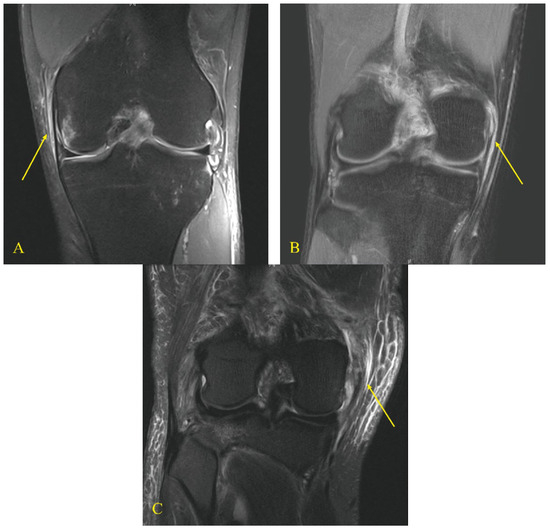

- Naraghi, A.M.; White, L.M. Imaging of athletic injuries of knee ligaments and menisci: Sports imaging series. Radiology 2016, 281, 23–40. [Google Scholar] [CrossRef]